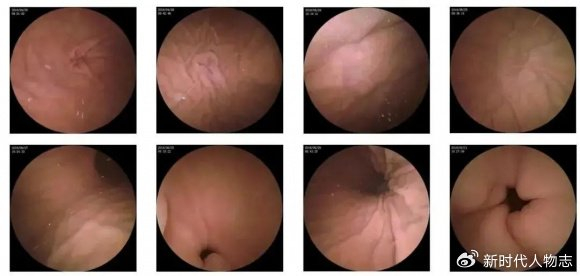

摘要:本文介紹了肛門息肉早期的圖片和相關(guān)介紹。肛門息肉是肛門部位的一種常見病變,早期發(fā)現(xiàn)對于治療具有重要意義。文章通過圖片展示了肛門息肉的早期形態(tài),并簡要介紹了其癥狀、原因、診斷和治療等方面的信息,以幫助人們更好地了解和認識這一疾病。

肛門息肉早期圖片展示

(請在此處插入肛門息肉早期圖片)

圖片展示可以幫助公眾更直觀地了解肛門息肉的外觀和癥狀,請注意,由于個體差異和拍攝角度等因素,圖片僅供參考,不能作為診斷依據(jù)。

2、內(nèi)窺鏡檢查:通過結(jié)腸鏡或直腸鏡檢查,可以清晰地觀察到腸道內(nèi)的息肉。